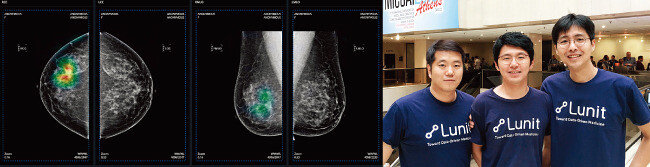

‘루닛’도 인공지능을 이용하는 이미지 인식 진단 기술 분야의 스타트업이다. 10월 중순 그리스에서 열린 의료영상 관련 국제 콘퍼런스의 유방암 병리진단 자동화 대회에서 스웨덴, 독일, 미국, 영국 등 선진국 기업을 제치고 3개 경쟁 분야에서 모두 1위를 차지했다. 흉부엑스레이를 통한 폐질환 검출의 경우 94% 정확성을 기록했으며, 좀 더 복잡하고 판독이 어려운 유방 촬영술도 80%대 정확성을 보여줬다.